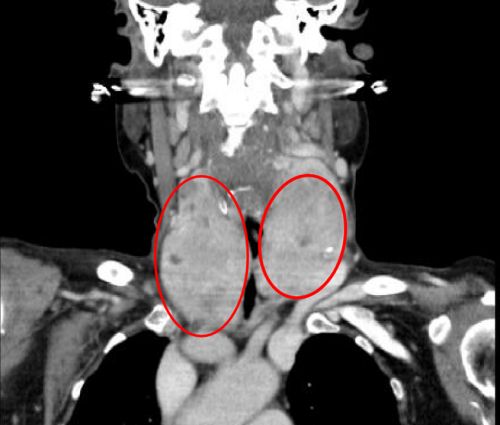

双侧巨大甲状腺肿瘤将气道挤压成一条细缝。

据主刀的肖旭平主任医师介绍,两个巨大的肿块“左右夹击”,导致颈段气管被压成了一条细缝,造成呼吸困难,术中极易出现窒息,给麻醉插管带来很大的风险。手术团队在精细操作的同时,巧妙利用肌肉间隙入路,既顺利切除巨大肿瘤,又减轻了创伤、缩短住院时间、有助于快速康复。